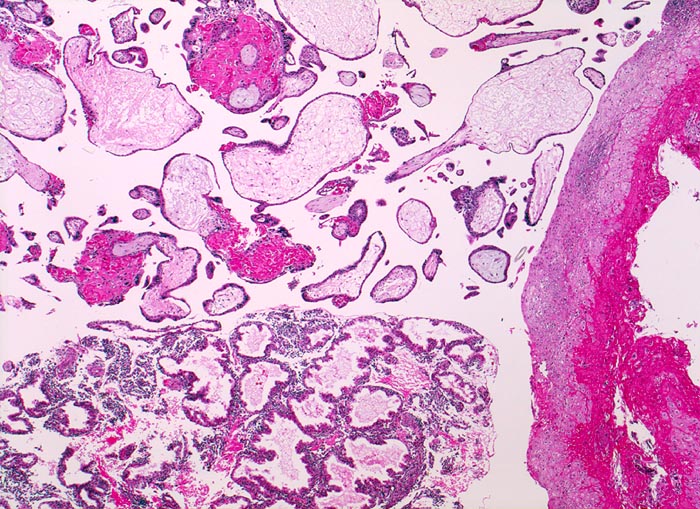

PathoPic – image database / PathoPic ID 4672 - Abortkurettage

Abortkurettage

Schwangerschaftsendometrium mit hypersekretorischen Drüsen. Deziduafragment mit Einblutungen. Plazentarzotten mit Zeichen der Retention ( hydropisches Zottenstroma, Fibrinablagerungen).

Missed abortion in der 11. Schwangerschaftswoche, sonographisch entsprechend der 9. Schwangerschaftswoche.

Plumpe Zotten mit hydropischem Stroma ohne Gefässe und flaches Trophoblastepithel sind vereinbar mit einer Windmole (=Windei). Differentialdiagnostisch könnten die beobachteten Veränderungen auch retentionsbedingt sein.